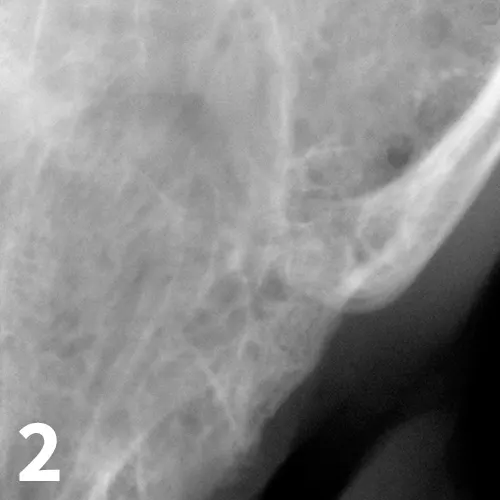

Dental radiograph demonstrating the removal of all tooth structures

Benny received preoperative buprenorphine and clindamycin and was anesthetized with sevoflurane. Buprenorphine was added to the traditional bupivacaine regional block in all 4 quadrants to extend the analgesia time.10,11 Radiography was used to rule out retained roots from previous surgeries and periodontitis, which may contribute to ongoing inflammation. Based on previous results and the symmetric inflammatory typical gingivostomatitis pattern, repeat biopsies were not performed. Benny’s remaining teeth were surgically extracted with quadrant flaps elevated, tooth structure completely removed and confirmed radiographically (see Figure 2), emptied alveoli debrided and lavaged, gingival edges freshened, and the flap closed without tension with a resorbable monofilament suture. Following the surgery, Apex Dog and Cat Dentistry’s nontraditional therapy was instituted (see Novel Therapy).